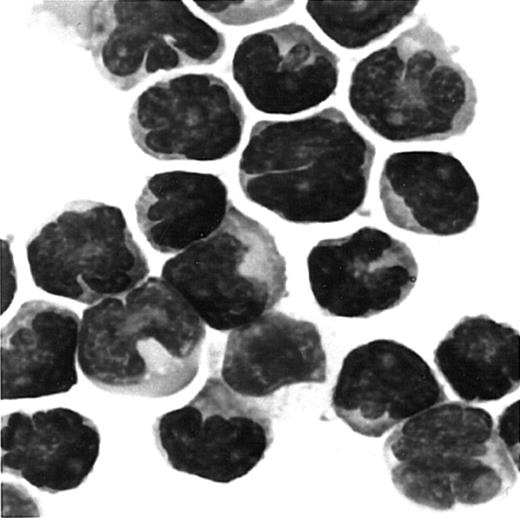

We next examined whether fresh ATL cells were capable of responding to the CCR4 ligands, TARC/CCL17 and MDC/CCL22,15 16 in a chemotactic assay using a Transwell plate. A total of 8 ATL cases (4 acute and 4 chronic) were studied. Representative results are shown in Figure5. We observed an efficient migration of PBMCs from all patients with ATL (8/8) toward TARC and MDC with a typical bell-shaped dose-response curve and an optimal concentration of about 1 nM. No such vigorous migration was observed by using fresh PBMCs from healthy adult donors in the present conditions. Thus, it is likely that the responding cells were mostly leukemic cells. To confirm this, we carried out a cytologic evaluation of cells migrated into the lower chambers. As shown in Figure 6, Giemsa staining of cytospin samples confirmed that migrated cells from PBMCs of patients with ATL were indeed mostly abnormal cells with characteristic flowerlike nuclei. Thus, fresh ATL cells expressing CCR4 are capable of efficiently responding to the CCR4 ligands TARC and MDC.

Giemsa staining of cells migrated to MDC/CCL22.

PBMCs were obtained from a patient with ATL. Cells migrated to MDC in chemotaxis chambers were collected and stained with Giemsa as described in “Materials and methods.” Original magnification, × 1000.